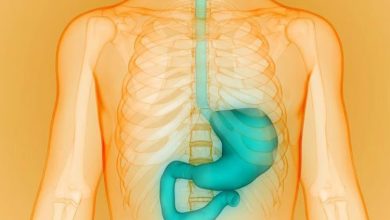

روش زاپینگ معده از طریق کاهش اشتها منجر به کاهش وزن میشود

lastech - به گفته محققان، این بخشی از معده است که گرلین، هورمون اولیهای که اشتها را کنترل میکند را…

lastech - به گفته محققان، این بخشی از معده است که گرلین، هورمون اولیهای که اشتها را کنترل میکند را…